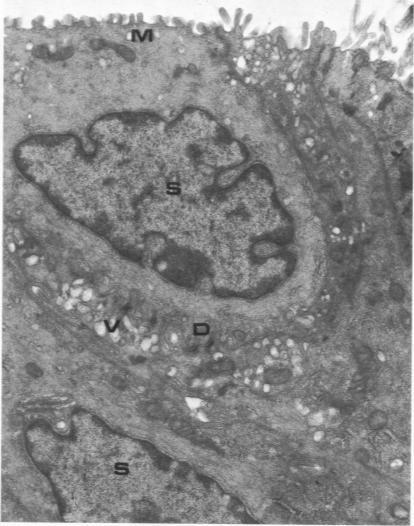

The major bronchi of swine, a dog and rabbits were examined with a scanning electron microscope and the fine structure of the openings of bronchial glands were studied three-dimensionally. The smallest areas of squamous metaplasia involved the duct openings. By examining serial sections with the light and transmission electron microscopes these early lesions were found localized at the opening of the bronchial gland duct. Cells intermediate to goblet and squamous cells were present in these lesions. Squamous metaplasia starting at this particular location is probably common and metaplasia can be an intracellular process.

用扫描电子显微镜检查了猪、狗和兔子的主支气管,并对支气管腺开口的精细结构进行了三维研究。鳞状化生面积最小的区域涉及导管开口。通过光学显微镜和透射电子显微镜检查连续切片,发现这些早期病变局限于支气管腺导管开口处。在这些病变中存在介于杯状细胞和鳞状细胞之间的细胞。从这个特定位置开始的鳞状化生可能很常见,并且化生可能是一个细胞内过程。